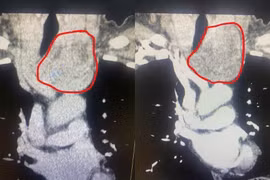

Bướu giáp khổng lồ là bệnh lý hiếm gặp, khối u kích thước lớn ảnh hưởng đến thẩm mỹ và chất lượng cuộc sống như gây khó nuốt, khó thở, run tay, khàn giọng… Phẫu thuật bướu giáp khổng lồ tiềm ẩn nhiều nguy cơ và tai biến.

Bệnh nhân S.B. 20 tuổi (Gia Lai) có khối bướu giáp từ nhỏ, nhưng không điều trị, gần đây bướu to chèn ép khiến anh khó thở, nuốt khó, không thể cúi,...